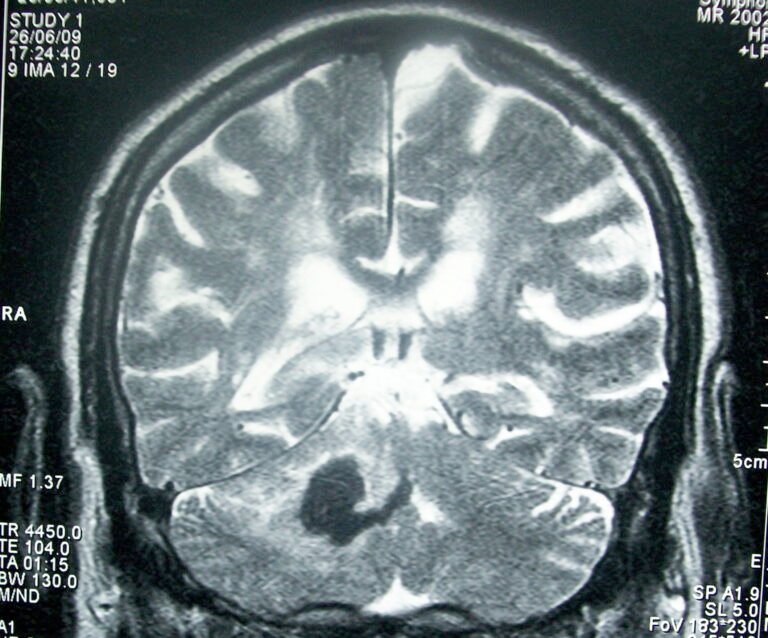

Día Mundial del Accidente Cerebrovascular

El Día Mundial del Accidente Cerebrovascular (ACV) se conmemora cada 29 de octubre y está dedicado a aumentar la conciencia …